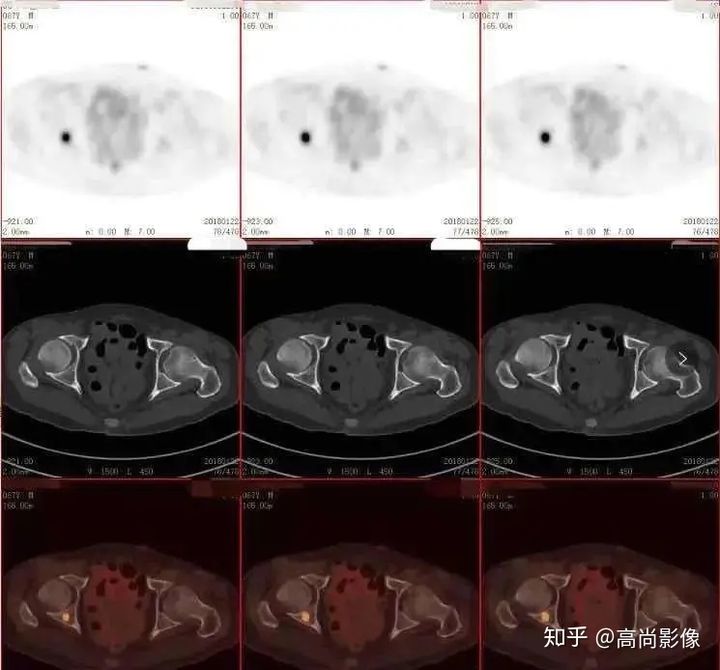

(右側(cè)髖臼骨轉(zhuǎn)移)